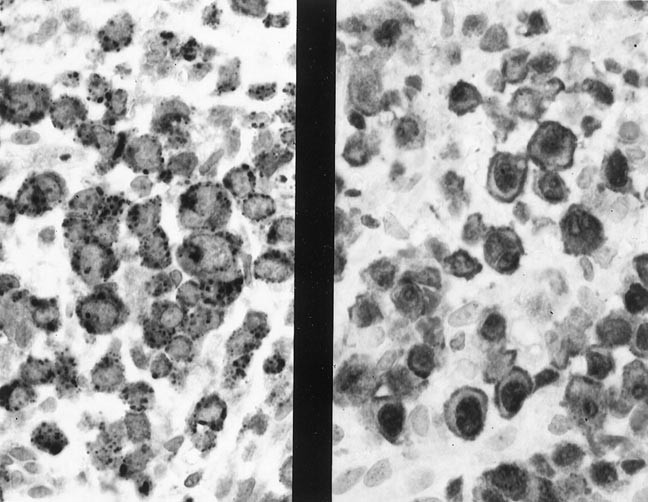

A nodular proliferation of atypical clear cells of intermediate size with abundant interspersed histiocytes was present in the malignant T-cells and infiltrated the breast parenchyma and fat (Figs. 3 and 4). The lymphoma seemed to follow the lobular breast architecture and the associated fibrosis accentuated in the striking nodularity. The axillary lymph node showed effacement of the architecture by the same infiltrate seen in the breast tissue. Numerous epithelioid histiocytes were seen throughout the malignant cells of the lymph node. Because of the numerous epithelioid histiocytes, the case initially was diagnosed as a peripheral T-cell lymphoma, lymphoepithelioid cell (“Lennert's” lymphoma); we reclassified the case as PTCL, medium cell. Immunohistochemical studies showed that the malignant cells were immunoreactive with CD45RB, CD3, CD45RO, βF1, CD43, CD8, and TIA-1. Rare cells were immunoreactive with CD30. CD56 was weakly immunoreactive in 20% of the cells. The cells were negative with CD20, CD4, TCR δ-1, and cytokeratin. CD20 highlighted sparse B cells, which were found at the periphery of the nodules in the breast. No evaluation for LE components could be made in the breast mass because the unstained slides were limited. The TCR γ assay showed a monoclonal band. The IgH assay and TCR β assays showed no monoclonal band.